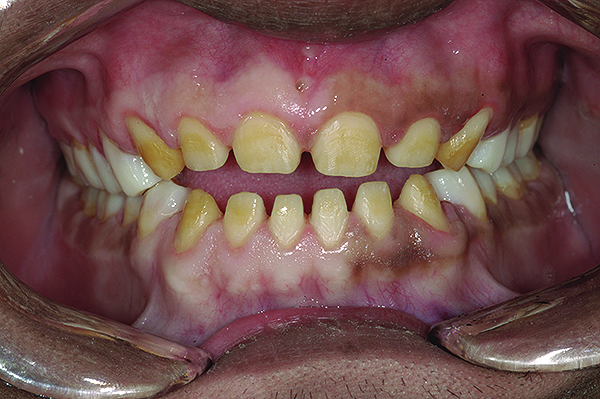

Figure 5. Preoperative 1:1 retracted frontal view.

Figure 5